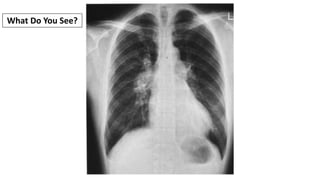

What Do You See?